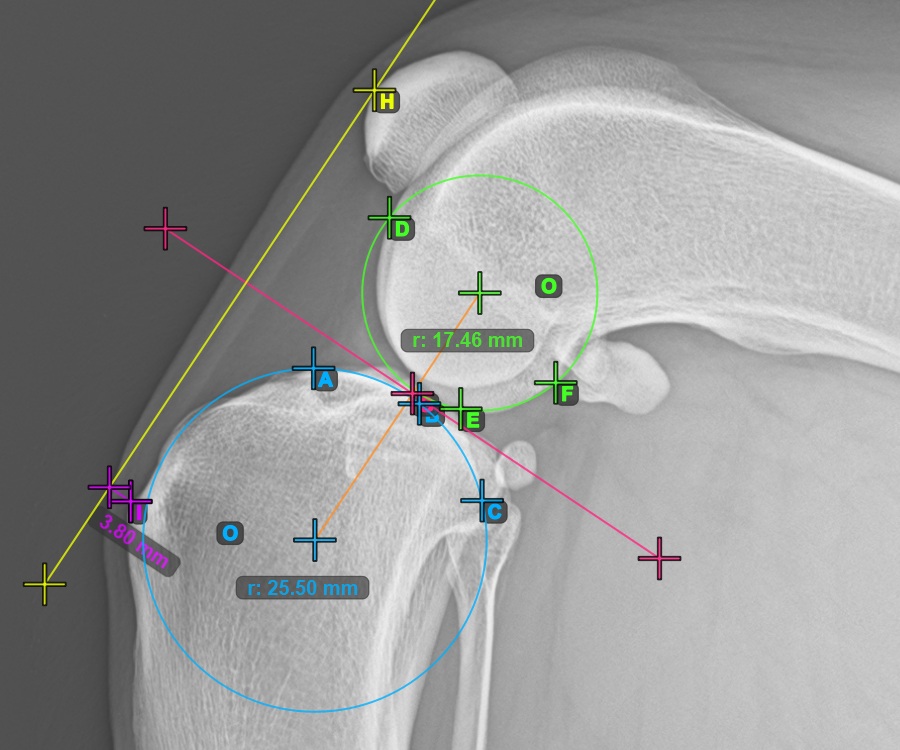

Start the TTA measurement procedure by marking the most cranial point of the Patella.

The image below depicts the usual placement of the most cranial point of the Patella.

To complete the TTA - 1 Condylus variant of TTA measurement procedure mark the most dorsal point of the Crista Tibiae (Tuberositas Tibiae). The distance between the Tuberositas Tibiae and the line passing along the most cranial point of the Patella is the required adjustment for the TTA procedure.

The image below depicts the usual placement of the tibial tuberosity, the most prominent point of the tibial crest.